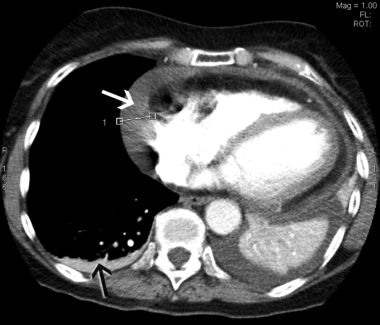

In view of the recent cholecystectomy, the patient underwent repeat CTPA, which excluded a pulmonary embolus but revealed a moderate pericardial effusion measuring up to 2.1 cm laterally and small bilateral pleural effusions (Box 2). An echocardiogram confirmed the pericardial effusion but showed no evidence of cardiac tamponade. Inflammatory markers were markedly elevated, with a C-reactive protein level of 290 mg/L (RR, < 12 mg/L) and an erythrocyte sedimentation rate of 103 mm/h (RR, < 21 mm/h). The patient had low-grade anaemia (haemoglobin level, 96 g/L; RR, 115–165 g/L), but this improved to 116 g/L without treatment. Her white cell count was elevated at 16 × 109/L (RR, 4–11 × 109/L), with predominant neutrophilia, and her platelet count was significantly elevated at 800 × 109/L (RR, 150–400 × 109/L). Renal function, urinalysis, autoimmune markers and a repeat troponin I measurement were normal. These findings were consistent with a diagnosis of Dressler’s syndrome.